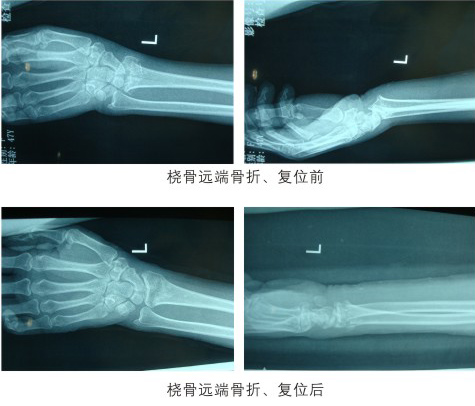

科室图片

来源:本站原创 发布时间:2018-02-13 09:55:58